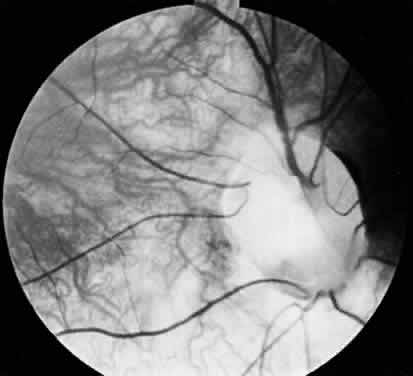

In optic nerve coloboma (Fig. 7) the optic disc is enlarged, frequently oval vertically, and excavated.57 The colobomatous defect may involve the entire disc or just the inferior portion. The excavated region is decentered inferiorly and may extend to involve the choroid and retina. When it does, the eye is often microphthalmic.57 When the entire disc is involved, the inferior region is excavated to a greater extent than the remainder of the disc, confirming its colobomatous nature. The retinal vessels may radiate from the disc in a spokelike fashion, with fewer bifurcations than normal.57 An association between optic nerve colobomas and basal encephaloceles has been reported58,59; however, examination of the literature reveals only a few photographically documented cases, and the reported association may be because of its confusion with morning glory disc anomaly.60,61

Fig. 7. Optic nerve coloboma.

Vision in the presence of a colobomatous defect can range from normal to no light perception. The degree of vision loss is related to the location of the defect and the presence of any associated abnormalities. Isolated iris colobomas do not usually affect visual acuity, whereas optic nerve colobomas almost always lead to some reduction in vision. If a chorioretinal coloboma is located in the posterior pole, an associated staphyloma may cause disturbance of the macula with resultant poor vision.